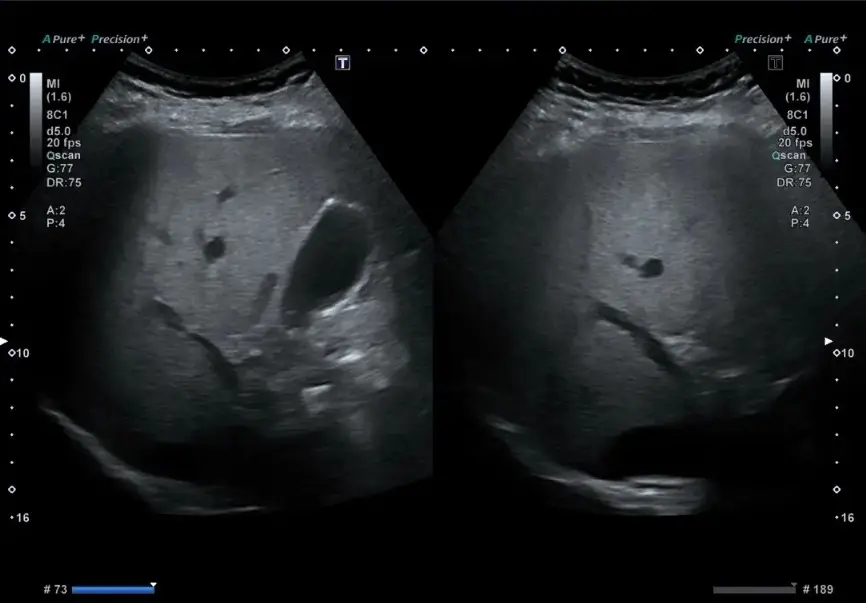

Figure 9: An ultrasound of a patient with MASLD. Common findings include an enlarged liver, increased brightness due to the presence of fat droplets within the liver cells, and blurring of the blood vessel and ductal appearance.